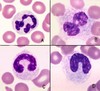

Describe the prominent process occuring

Erythrophagocytosis